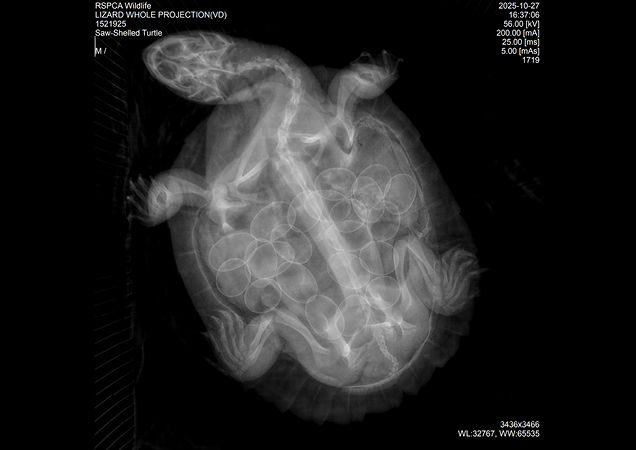

Late last year, our RSPCA Rescue Team attended a call about a saw shelled river turtle that had been hit by a car. Arriving at our RSPCA Wildlife Hospital in Brisbane, the turtle was no spring chicken - likely around 50 years of age!

Named Mira, this poor turtle’s injuries were severe. She had fractures to both her top and bottom shell. Painful and complex with a long road to recovery. But that wasn’t all…

A radiograph revealed that this old mother was carrying 22 eggs!